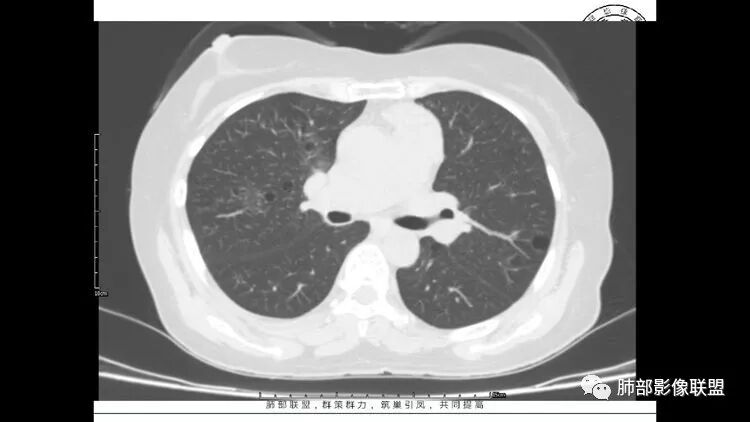

胸CT:1.双肺多发囊性变,以中下肺为主,病变边缘可见肺动脉,部分囊内可见分隔及肺动脉,双下部分肺野周围可见小叶中心结节及树丫征。

2 左肺上叶尖后段 右肺上叶前段 右肺下叶外基底段 结节影,边界清楚,可见柔软毛刺,左肺下叶后基底段混合密度影。

3.纵隔淋巴结肿大?,以主动脉弓为界向上向下增大。

多发气囊,气囊内可见血管进入,因患者眼干伴类风湿,可能有干燥综合征,那LIP可能性大。因为不是育龄期发病,可排除LAM。患者左纵膈淋巴结肿大,且有融合趋势,结合左下肺病灶,考虑合并恶性肿瘤,淋巴瘤?鉴别结节病

1.左下肺腺癌;2.两肺弥漫性病变(多发囊腔、部分囊壁不规则,分布无特异,结节,空洞,树芽征,GGO),结合眼部情况首先考虑LIP,不典型感染(病毒或其他)待排。

左肺下叶混杂密度病灶,其内可见空泡,周围ggo清楚,考虑浸润性腺癌。双肺散在多发薄壁囊腔和实性结节,以胸膜下及血管旁分布位于,气囊可见血管贴边征,双肺小叶间隔及中央间质增厚,局部可见磨玻璃影及树芽征,纵隔内淋巴结肿大,考虑LIP

综上,考虑左下肺浸润性腺癌+LIP

老年女性,长期使用激素史。双肺多发散在斑片状磨玻璃密度影及大小不等的薄壁含气囊腔,下肺相对较多较大。双肺多发结节,左肺上叶结节相对较大,界清,边缘光滑,分叶不明显。右肺下叶前外底段散在树丫。前上纵膈偏左侧不规则软组织团块,颗粒感,偏软。肺内囊腔及磨玻璃影考虑淋巴细胞间质性肺炎,或淋巴管肌瘤病。纵膈团块考虑淋巴管瘤。两者结合,考虑淋巴细胞增生病变。右肺下叶散在树丫,结核待排。双肺结节性质待定。

双肺多发散在斑片状磨玻璃密度影及大小不等的薄壁含气囊腔,下肺相对较多较大。双肺多发结节,界清,边缘光滑,分叶不明显。右肺下叶前外基底段散在斑片树芽。前上纵膈偏左侧不规则软组织团块,密度不均,其内可见不规则纤维样低密度,周围簇状小淋巴结。考虑1淋巴细胞间质性肺炎。2考虑纵膈胸腺淋巴瘤。

LIP影像重要线索一句话:

双肺下叶分布为主的间质改变(磨玻璃影、小叶间隔增厚)、散在气囊影(常有血管贴边)、边界不清小结节